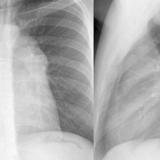

Case 9 Thymoma Lat

Case 9 Thymoma PA